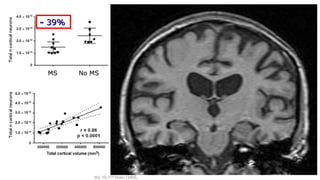

-- 39%39%

MSMS No MSNo MS

Carassiti D et al. Neuropathol Appl Nerobiol 2017; doi: 10.1111/nan.12405.doi: 10.1111/nan.12405.

Grey matter volume loss and disabilityGrey matter volume loss and disability

Fisniku, et al. Ann Neurol 2008Fisniku, et al. Ann Neurol 2008

n= 73 patients with initial diagnosis CIS, followed up for 20 yearsn= 73 patients with initial diagnosis CIS, followed up for 20 years